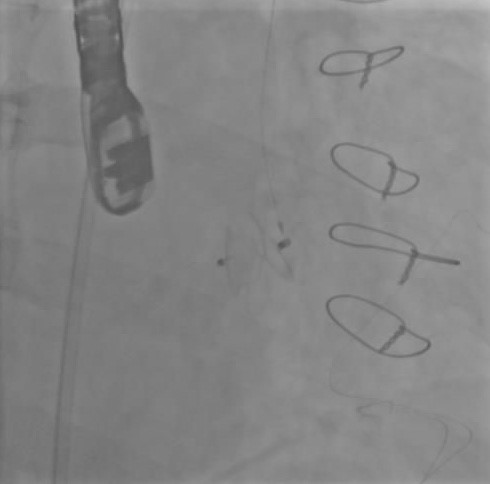

Balıkesir’de ilk nitelikli işlemlerin bir yenisi de Kardiyoloji Anabilim Dalı bünyesinde girişimsel kardiyoloji ile gerçekleştirilen paravalvüler kaçak kapatılması işlemi oldu. İşlem sırasında hastanın kalbi durdurulmadan ve göğüs kafesi kesilmeden, kasığından girilerek yapay kalp kapağındaki kaçak ameliyatsız kapatıldı.

Yapılan işlemi gerçekleştiren ekipte yer alan Prof. Dr. Halil Kısacık, Doç. Dr. Eyüp Avcı, Doç. Dr. Tarık Yıldırım ve Doç. Dr. Özgen Şafak konu hakkında açıklamalarda bulundu. Daha önce kalp kapakçığı değişim ameliyatı olan hastada takılan kapağın kenarından ayrılmasıyla kan kaçağı (paravalvuler leak) meydana geldiğini belirten öğretim üyeleri, Kardiyoloji Anabilim Dalına başvuran hastaya, Türkiye’de sayılı kalp merkezinde yapılan ve önemli düzeyde cerrahi deneyim gerektiren paravalvüler kaçak kapatılması işlemi uygulandığını dile getirdi. İşlemin sadece girişimsel kardiyologlar tarafından yapıldığının altını çizen öğretim üyeleri, işlem sırasında hastanın kalbi durdurulmadan ve göğüs kafesi kesilmeden, kasığından girilerek yapay kalp kapağındaki kaçağın ameliyatsız kapatıldığını söyledi.